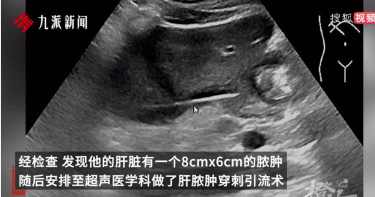

陸男高燒3週不退 醫師傻眼:你肝臟裡插了支牙籤

近日,中國杭州一名男子因為高燒多日不退就醫,檢查後發現肝臟裡有顆膿腫,害他得了膿毒血症。醫生深入追查下發現,這顆長在男子肝臟上的膿腫,竟然是因為一支牙籤「插」進了他的肝臟所造成。最終透過手術取出男子體內的牙籤,他才終於恢復了健康。據中國杭州《每日商報》報導,一名家住杭州的高姓男子日前突然發起了高燒,而且一燒就長達3個禮拜,體溫更是飆高到39度,還時常伴隨著上腹部疼痛。高男到杭州師範大學附屬醫院就診,檢查後發現他的狀況是「膿毒血症」。進一步的檢查後發現,他的肝臟上竟然有一個8x6公分的膿腫。醫生替他做了肝膿腫穿刺引流術,將膿液放掉後,才發現在他肝臟膿腫處插了一根牙籤。經過醫療團隊的詳細詢問,高姓男子才回想起來,此前某次飯局上喝得大醉,醒來後就感覺肚子不適。可能是那次喝醉後,習慣性拿牙籤剔牙,卻神智不清的牙籤吞下。杭州師範大學附屬醫院的醫師推斷,可能是那次高姓男子誤吞了牙籤,牙籤進入了胃後又穿透了胃壁,插進肝臟從而形成了肝膿腫。當膿腫消退後,被膿液包裹著的牙籤自然就顯現出來了。之後,高姓男子接受了腹腔鏡下肝部分切除術加異物去除術,終於把體內的牙籤取出,在經過幾天的護理,終於順利出院。肝膿腫是細菌、溶組織阿米巴原蟲、真菌等微生物引起的肝臟化膿性病變,若不積極治療,死亡率可高達10%至30%。高先生吞入的牙籤刺破胃壁,導致消化道細菌的移位,從而導致肝臟膿腫。杭州師範大學附屬醫院醫療團隊提醒:在進食時要細嚼慢嚥,特別是在飲酒後也要注意,有些人喜歡叼著東西或用牙籤清理牙齒,這些尖銳的物體一旦掉進肚子,如果不能順利排除,就會造成胃腸道穿孔,甚至危及生命。此外,若意外吞服異物,應保持冷靜,盡速就醫,以免因為延誤治療對身體造成更大傷害。